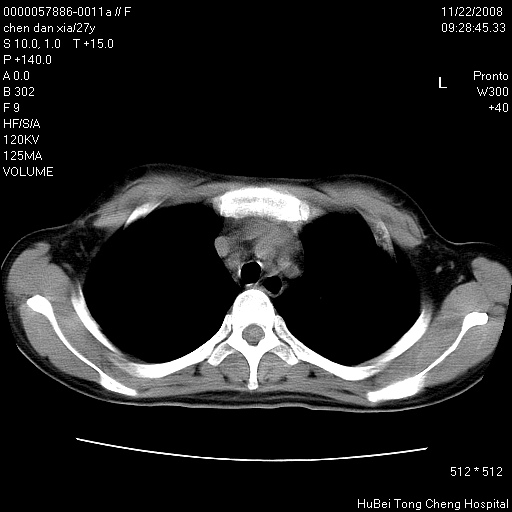

标题: CT16752:F,27Y。发热咳嗽20余天,伴盗汗。 [打印本页]

标题: CT16752:F,27Y。发热咳嗽20余天,伴盗汗。

气管前腔静脉后淋巴结肿大 右肺门纹理模糊

淋巴结核?

右下肺见片絮状影,两肺野内分布不均的小结节影,结核并肺内播散可能性大,建议结合实验室检查 .

右下肺纹理模糊;纵隔可见肿大淋巴节;右心缘旁结节,边缘光滑,纵隔窗病变范围较肺窗明显小,首先考虑右下肺结核,不排外淋巴瘤

双肺纹影普多,部分呈网状,支炎或淋巴管炎?

纵隔内淋结肿

局部胸膜增厚